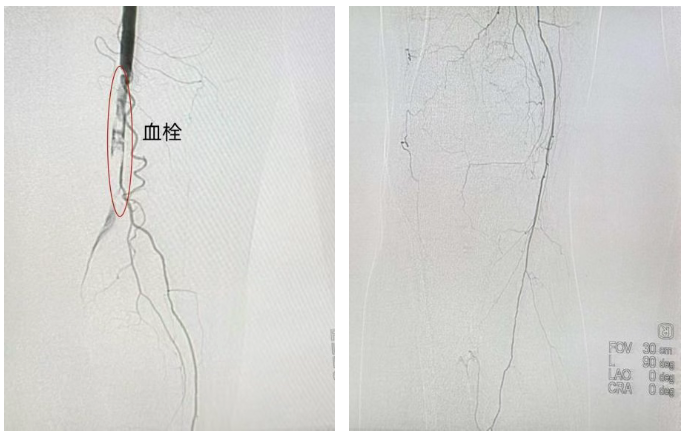

面对一位86岁高龄患者,传统开放取栓手术创伤大、风险高。夏风飞主任团队快速评估后,决定采用以机械旋切系统为核心的微创介入方案,力争以最小创伤实现最快再通。手术在局部麻醉下通过大腿根部微小穿刺进行。术中血管造影清晰显示股浅动脉及腘动脉内长段血栓栓塞,血流中断,侧枝血管供应小腿。

在血栓负荷基本清除后,团队进一步行球囊扩张及支架植入术处理狭窄的血管基础病变。术后即刻造影显示,股浅动脉及腘动脉血流通畅,远端胫后动脉及腓动脉显影良好。